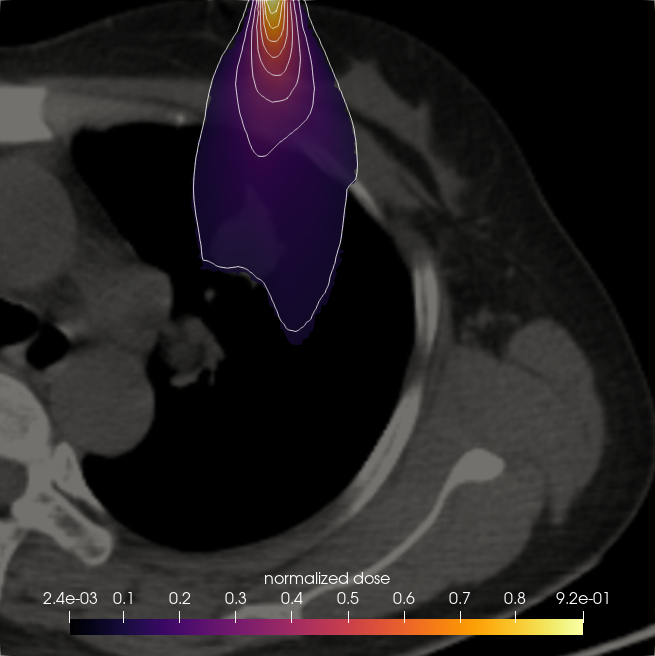

7.3. Beam in 2D patient CT

Having validated the CSD solvers against StarMAP and a Monte Carlo framework in section 7.1, we now examine a realistic 2D CT scan of a lung patient as a proof of concept for the application of our framework to radiation therapy computations. The patient data was retrieved from an open source data set (Li et al., 2020) in The Cancer Imaging Archive (TCIA) (Clark et al., 2013). The patient is irradiated with an electron beam of MeV. We model this beam as the initial condition

where is the beam position within the domain and is the beam direction. The remaining parameters are chosen as . To determine a tissue density for given gray-scale values of the CT image, we set the maximum density, represented by white pixels, to the density of bone . The remaining tissue is scaled such that the minimum pixel value of zero corresponds to a minimal density of . This corresponds approximately to the lower bound of observed lung densities (Kohda and Shigematsu, 1989).

Figure 14 compares the normalized dose for a CSD , and solver. While all methods show similar behaviour and are able to capture the effects of heterogeneities in the patient density, some differences e.g. in the maximum depth of the solution compared to and or the shape of the lowest two isolines can be observed. The cross sections in figure 15 further show that the dose has a lower maximum and higher minimum value than the and to a lesser extent also solutions.